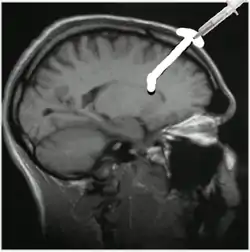

El dispositivo se implanta por medio de cirugía debajo del cuero cabelludo del paciente. El cirujano taladra un orificio mediante un buril en el cráneo a nivel del lóbulo frontal del cerebro e introduce el catéter del dispositivo a través del lóbulo del paciente en el ventrículo cerebral lateral. El depósito del dispositivo queda entonces situado encima del orificio del buril, por debajo de un colgajo de piel cabelluda; los fármacos se administran por inyección en el depósito.